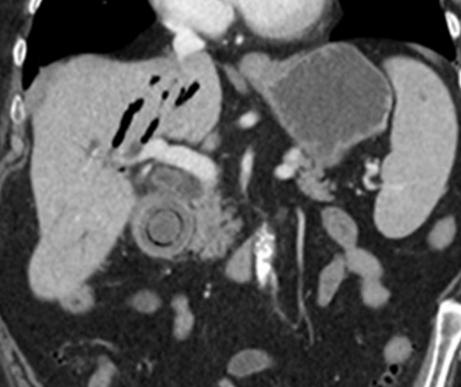

中年女性,因坐骨神经痛使用强的松治疗后出现恶心。冠状位 CT 示胃窦部偏心性增厚及粘膜下水肿,胃体部正常。内镜活检证实为急性胃炎。